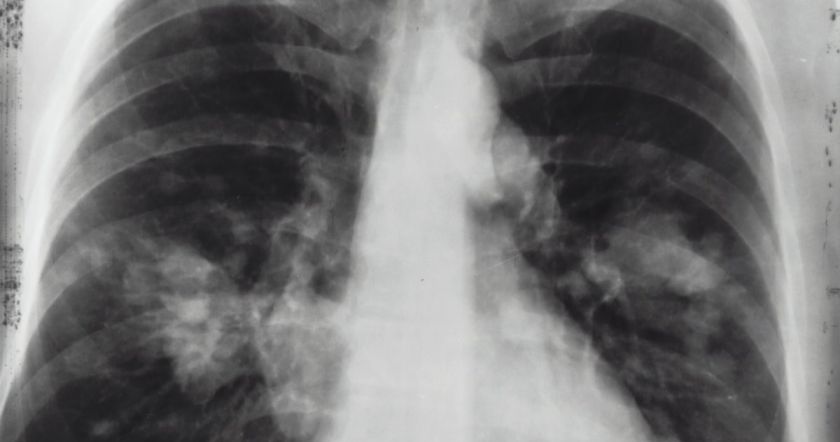

Рак легких является третьим по распространенности видом рака, но на него приходится наибольшее количество смертей от рака. Он также может быстро распространяться по телу, что делает его особенно смертельным. Многие люди знают о том, как болезнь может поражать легкие: среди некоторых симптомов присутствует постоянный кашель и хрипы, однако некоторые признаки могут проявляться и в других местах.